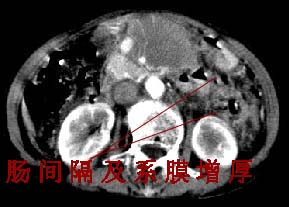

女:61岁.腹痛腹胀20天,行b超腹膜后实性占位.扫完后我查体发现患者右颈根部约3厘米类圆性包块,有移动{我考虑右颈根部包块是肿大淋巴结}.

ct:肝胃之间、胰头后、腹主a周围,融合而成团块状影,包绕血管,胰腺前移后缘分界欠清,与肝胃分界清,肿块未见明显强化,肝右叶后段小囊肿。

女:61岁.腹痛腹胀20天,行b超腹膜后实性占位.扫完后我查体发现患者右颈根部约3厘米类圆性包块,有移动{考虑右颈根部包块是肿大淋巴结}.

诊断:淋巴瘤>转移瘤。

1检查胃肠道2淋巴穿刺病检。

我的第1诊断还是考虑是淋巴类病变1}。从病灶形态上看不是很规则,但其更向是多个结节的融和,其内有少许坏死,整个病灶的强化不是很明显,临近左恻肠间隔有增厚,2}我认为更重要的一点的是肠系膜有明显增厚呈片状。3}患者的脾脏不大其未见异常病灶。结合以上几点我首先考虑是转移性{但对此诊断我觉得不足之处;转移性的淋巴结肿大融合为什么没有坏死?}。{另外患者无大便习惯改变及血便,其发现右颈包块在今年过年无意发现}。以上是我的浅分析望各位战友继续讨论!谢谢!!